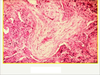

Lobar pneumonia on the left vs bronchopneumonia on right